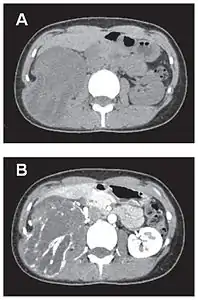

- Tumeur fibreuse solitaire du rétropéritoine

Aspect tomodensitométrique, sans (A) puis avec (B) injection de produit de contraste[44].